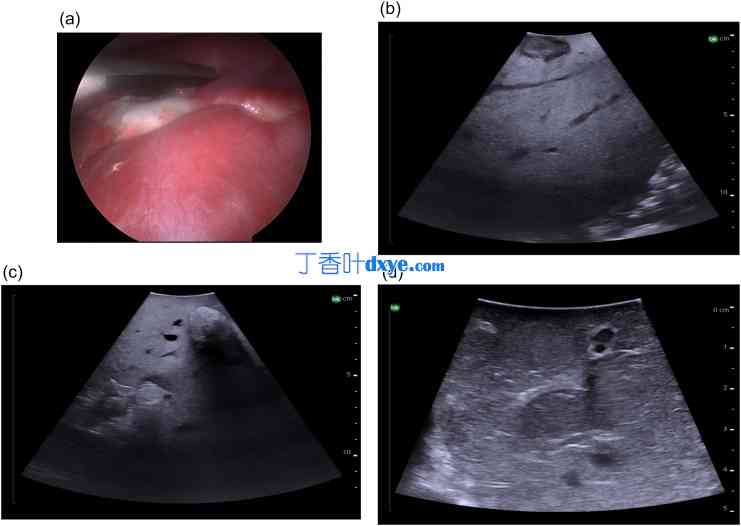

37.jpg

图 37

术中超声显示结直肠肝转移,a) 腹腔镜下纤维化的结直肠肝转移,b) 低回声转移,周围有低回声纤维化边缘,c) 高回声转移,d) 等回声转移。